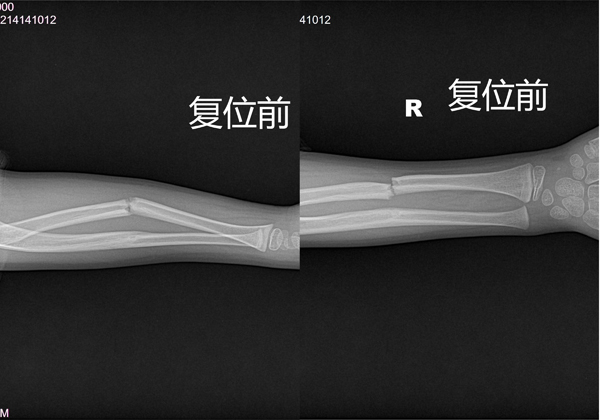

患者桡骨干骨折分离,合并尺骨骨裂。复位中存在桡骨骨折对位不好,尺骨断裂的风险,且桡骨断裂分离,复位失败存在手术风险。

复位前.jpg